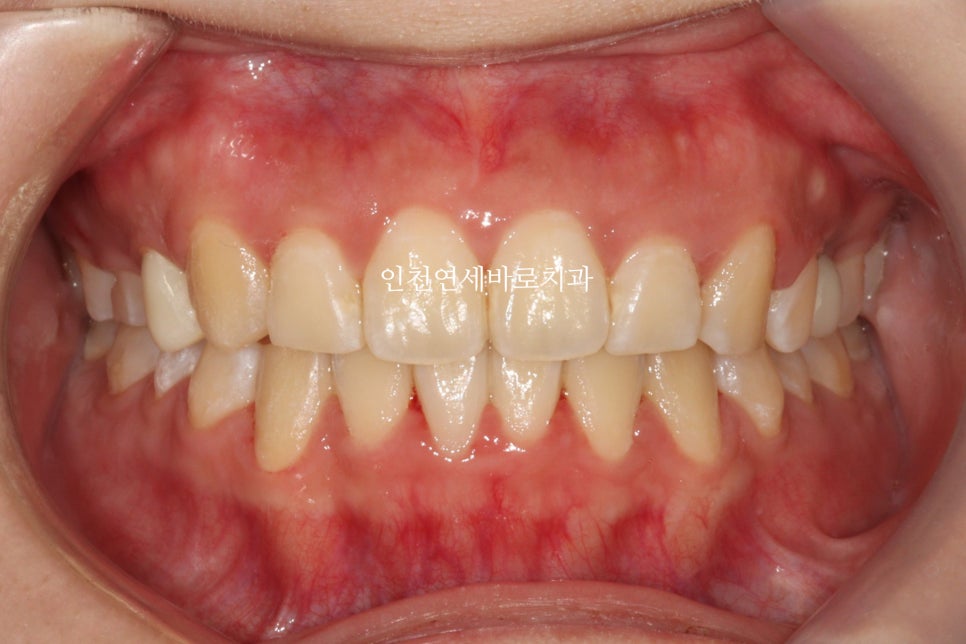

첫번째 세트가 끝났을때의 모습입니다.

교합이 맞지 않고 아쉬운 부분이 많이 보였습니다.

인비절라인으로 교합을 못 맞춘다는 말이 많은데 아닙니다

잘하면 당연히 맞아지죠